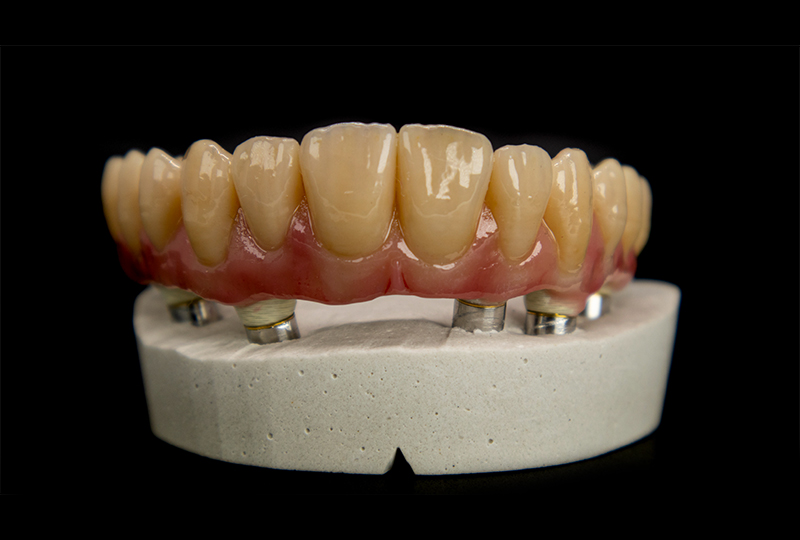

ODT Giovanni Rossi: Il paziente ci è ben noto, è una nostra conoscenza recente ma importante. Con lui abbiamo intrapreso un percorso di pianificazione chirurgica, riabilitato in carico immediato con una protesi stampata e caratterizzata nei toni rosa in composito.

Dopo alcuni mesi abbiamo finalmente raggiunto la completa maturazione dei tessuti e la perfetta integrazione degli impianti. Il paziente è soddisfatto del suo provvisorio, tanto da chiedere più volte: "Perché non lasciamo questa protesi? È perfetta!" (Figure 1, 2).

Fig. 1

protesi provvisoria a carico immediato dopo l'integrazione degli impianti

Fig. 2